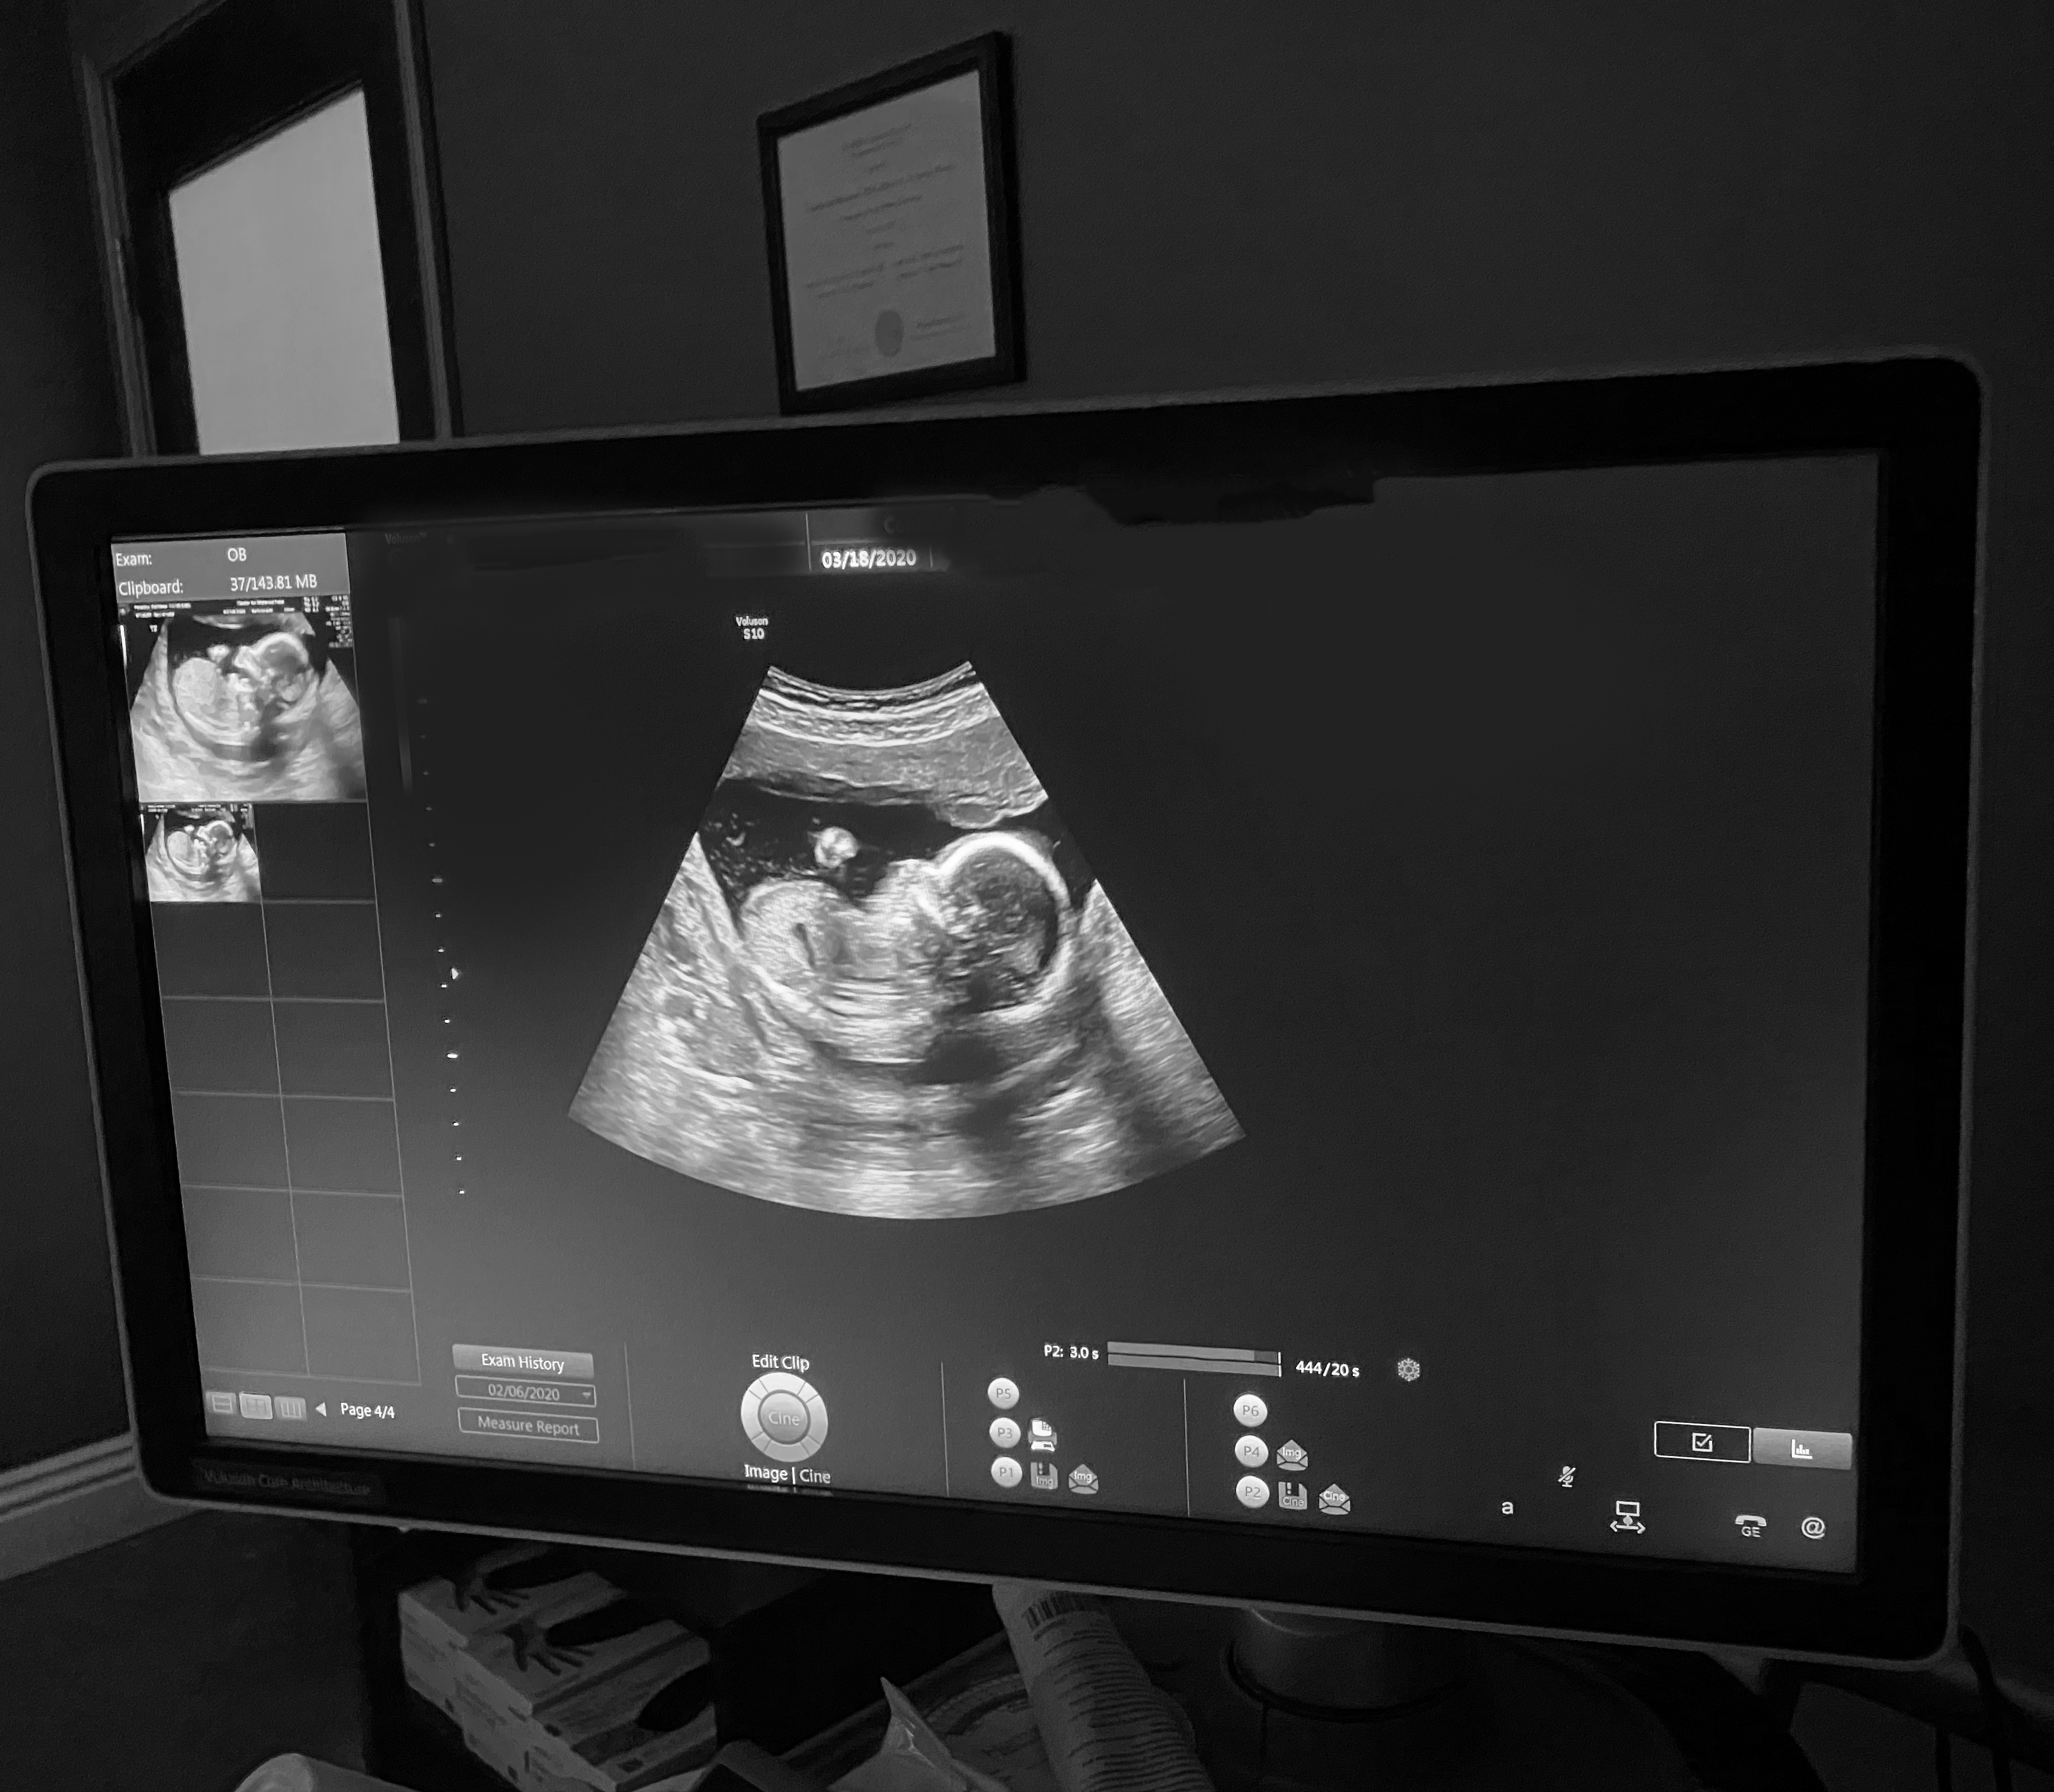

December 2019. That faint little second line that I saw on my early result pregnancy test, five days after my FET (frozen embryo transfer), wasn’t kidding. It got darker and darker as the days passed. And all of the sudden, I’m like any other pregnant lady -- headfirst into my first trimester, barely able to eat from nausea, taking two harcore naps a day and sobbing over animal rescue videos and sappy movies - even more than usual. Pregnancy hit me hard and fast. Though I felt like complete crap, I was so stinking happy.

The FET. No pain. You just lay there and watch on the big screen as they bring your thawed embryo into the room and finally give it a home. Then you lay there for about fifteen minutes, alone, trying to mentally will your baby to stick, aka not fall out or get lost or whatever else could go wrong up there.

Then you get dressed, go home and wait. And hope.

Four days later, I tested, and again the next day - and to the biggest shock in my life - I saw a very faint positive line. And that little thing turned into my BFP (big fat positive.)